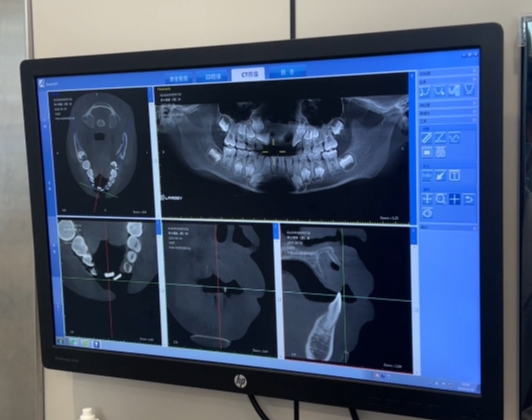

从小患儿CBCT影像中可以看出,他唇侧牙槽骨可见折裂影像,这代表牙槽骨出现骨折现象。但是,考虑到患儿11、21号恒牙脱离体内时间较长,到我院时已超过最佳植入时间30分钟,且正式开始牙再植手术时,牙齿脱出时长已大于2小时,但因患儿根尖尚未发育完成,当时我们与患儿家长沟通后,方案仍定为尝试性牙再植。